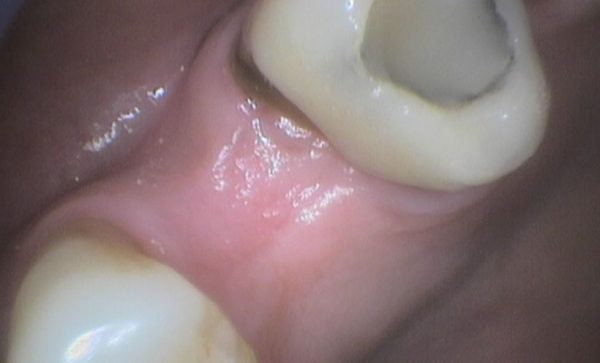

After -Abacus Dental After